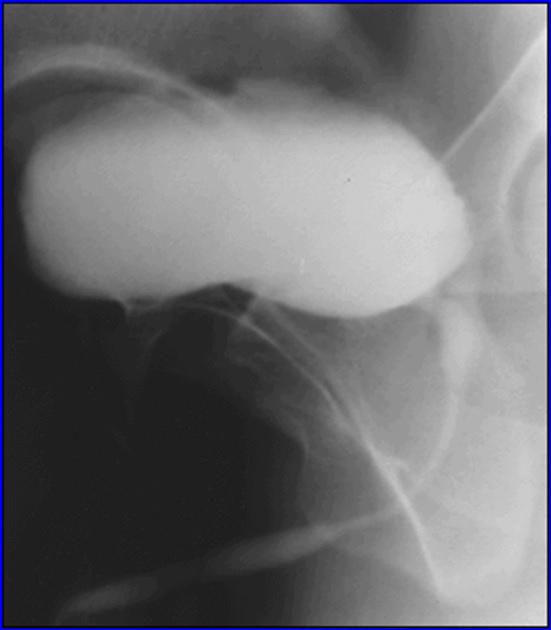

Bazinetul renal si ureterul, urografie - faza excretorie

Cisto-uretrografie micţională: